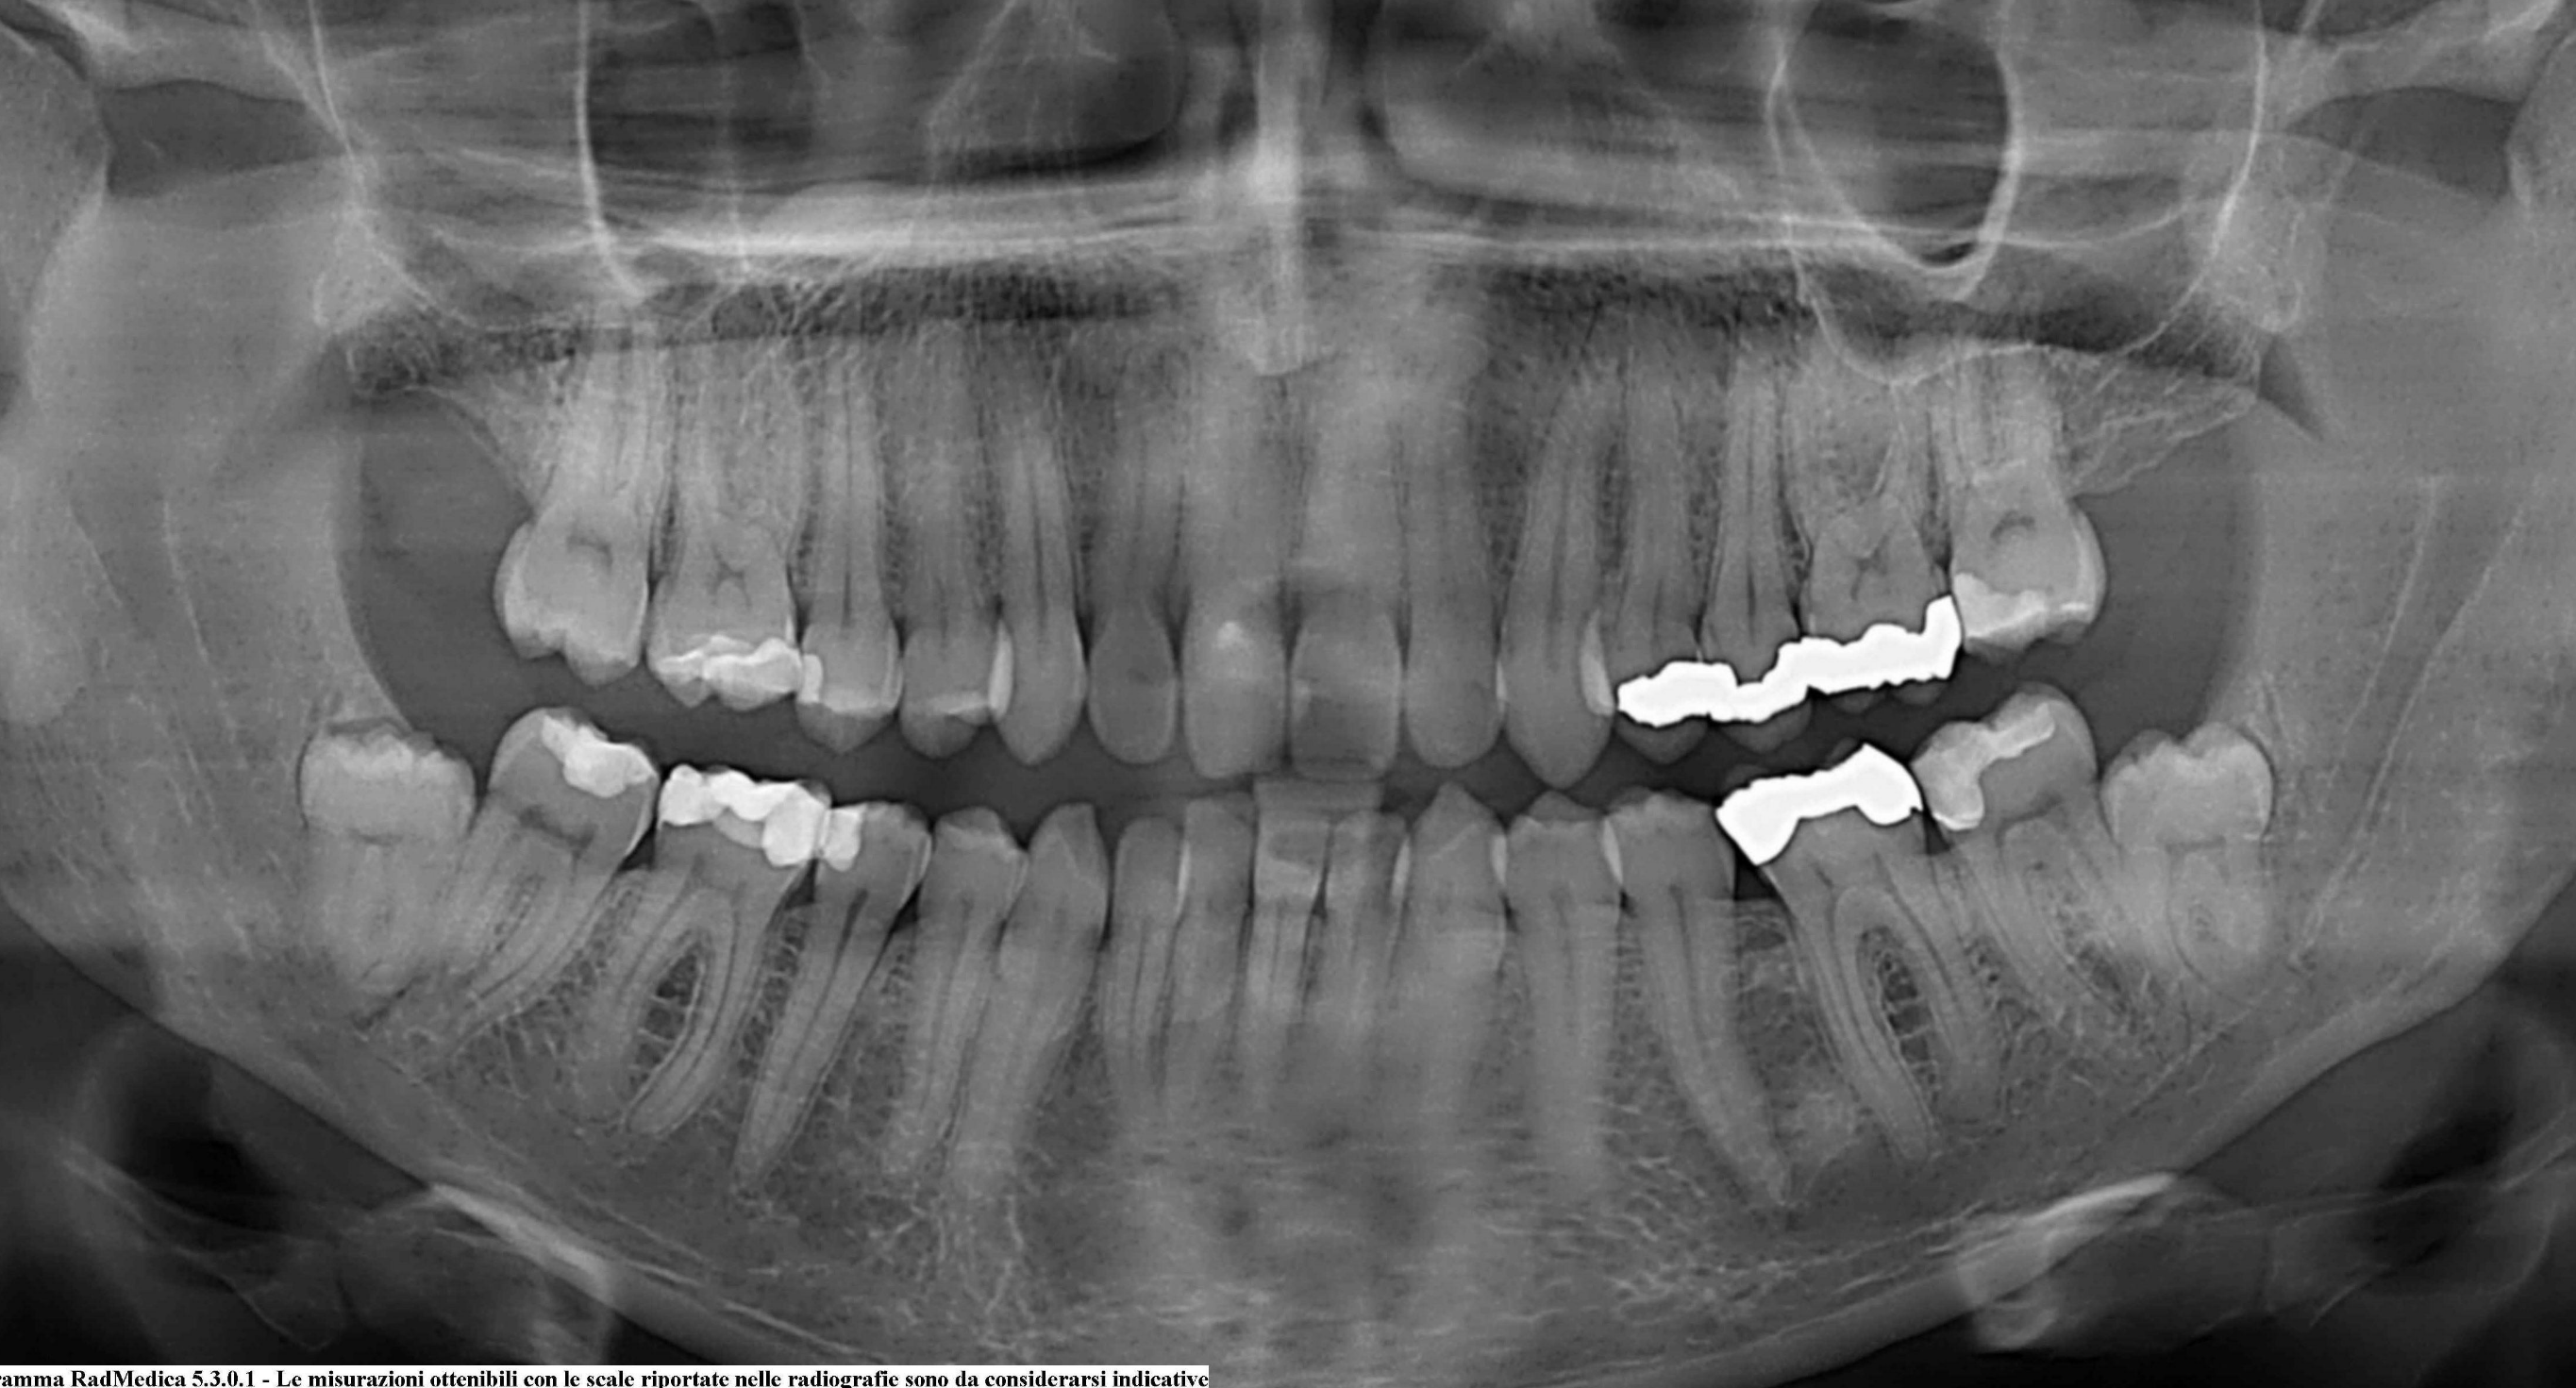

MI trovo in Germania e ho avuto pareri discordanti sulla mia ortopanoramica. Un chirurgo voleva levarmi tutti e quattro i denti del giudizio, la dentista mi ha suggerito di togliere i superiori.

Premetto tutti e 4 non mi danno nessun problema, ma quello superiore dx risulta cariato e l ho scoperto a seguito di una pulizia dentale.

Ciao Valentina, nel forum ci sono molti spunti al riguardo. Qui per esempio spiego quando ė giusto estrarli. I tuoi superiori vanno estratti, uno per la carie, ma anche l’altro perché sta scendendo e creerá problemi di vario tipo. Anche gli inferiori non sono felici, ma a vedere la radiografia non sembra abbiano un contatto vero coi denti che hanno davanti, fatto questo che li metterebbe a rischio. Comunque se volessi toglierli tutti e quattro, ti rassicuro che non presentano difficoltà di rilievo…nelle mani ovviamente di un dentista che sappia quel che fa.